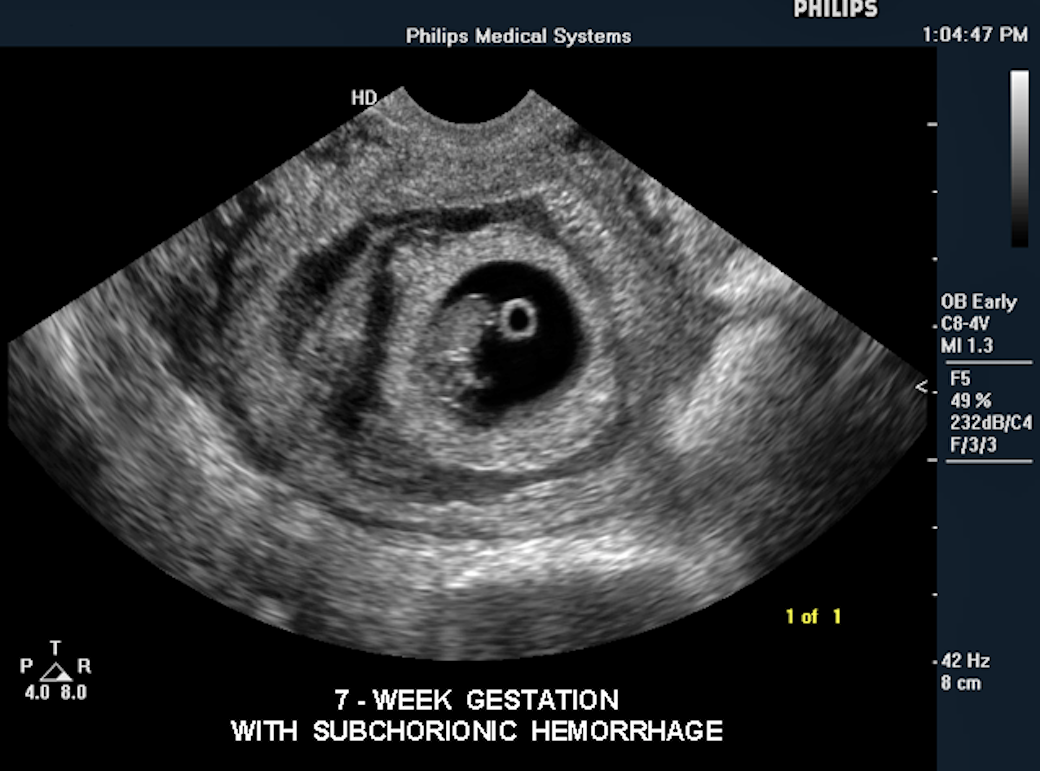

Ultrasound Wallpapers - Wallpaper Cave

wallpapercave.comultrasound hematoma subchorionic hemorrhage pregnancy fetal

wallpapercave.comultrasound hematoma subchorionic hemorrhage pregnancy fetal